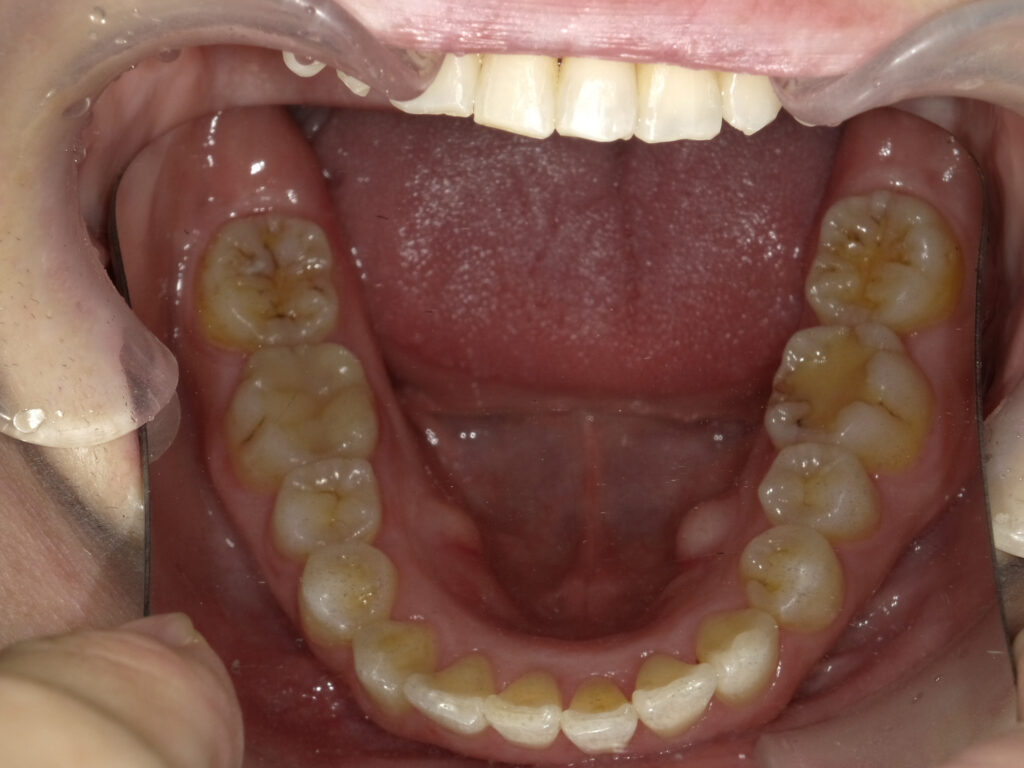

下顎

治療前